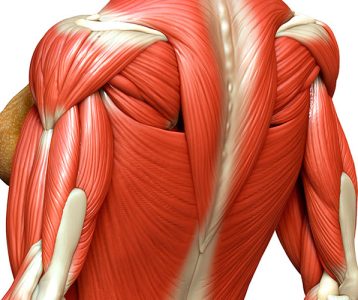

Em casos mais acentuados podem ocorrer quadros de dor, frequentemente relacionada à tensão muscular induzida pela curva – com a possibilidade de ser intermitente ou persistente. Ademais, esses indivíduos podem reportar fadiga muscular devido à constante tensão e limitação da amplitude de movimento, o que pode tornar a realização de atividades cotidianas mais desafiadoras.

“O tratamento deve ser personalizado, levando em consideração a sintomatologia e grau do desvio”, ensina o médico. Entretanto, em geral, a primeira abordagem é a fisioterapia, que envolve exercícios específicos para fortalecer os músculos das costas, melhorar a postura e reduzir a dor.